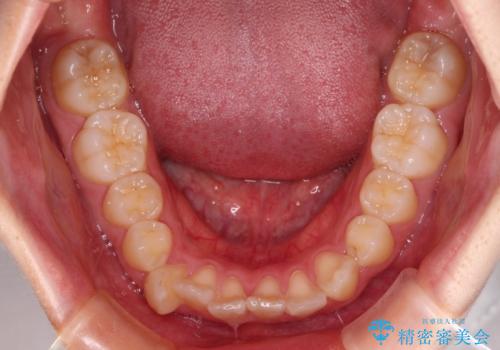

- メタルブラケット

- 1年9ヶ月

上下ともに歯列が前方に突出していたため、上下左右の第一小臼歯4本を抜去し、ワイヤー装置による矯正治療を行うこととしました。

上下左右4本抜歯する場合には、通常2年から2年半ほどの期間を要しますが、舌のトレーニングをしっかりと行っていただいたことで、1年9ヶ月で終了することができました。